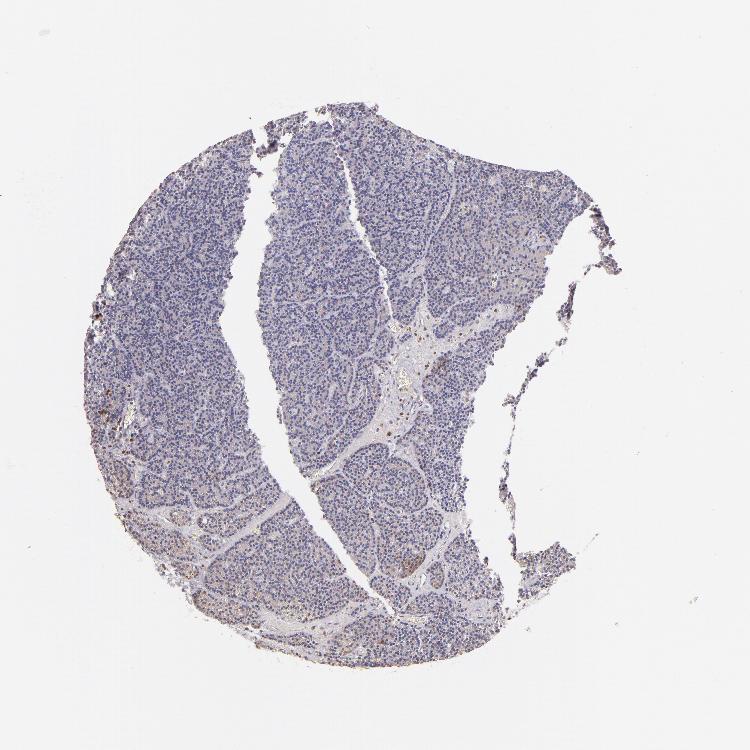

PARATHYROID GLAND - Antibody stainingi

Antibody staining in the annotated cell types in the current human tissue is reported as not detected, low, medium, or high, based on conventional immunohistochemistry profiling in selected tissues. This score is based on the combination of the staining intensity and fraction of stained cells.

Each image is clickable and will lead to virtual microscopy that enables deeper exploration of all samples and also displays staining intensity scores, fraction scores and subcellular localization as well as patient and tissue information for each sample.

Antibody HPA003134Antibody CAB002625

Glandular cells Not detectedLow